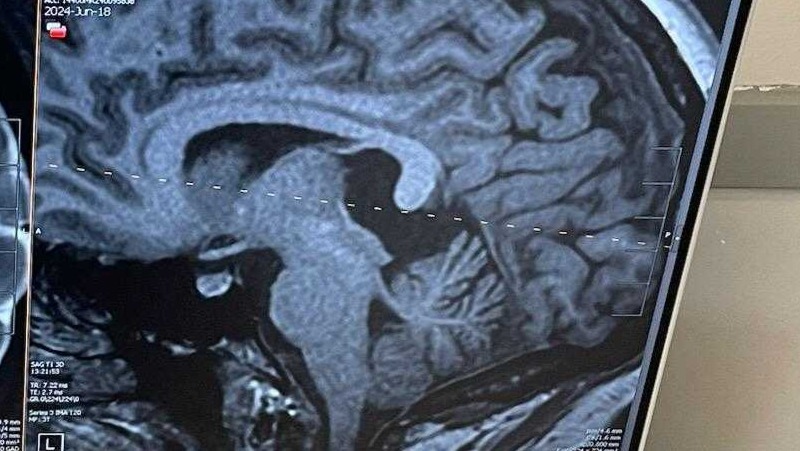

I’m reaching out for your support during a particularly challenging time for my wife, Sierra. In February, she tragically lost her father, and now she is facing another major hurdle: a rare 42 x 20 mm sized cyst in her brain that requires surgical removal. These recent events have been incredibly difficult for our family, but we are staying strong and focused on her recovery.

Before losing her father, Sierra had been going in and out of doctors visits for years with 12 ER visits just this year. As well as an ambulance ride. She has been suffering from headaches, dizziness, high blood pressure, high heart rate, nausea, trouble standing, uncommon fatigue, insomnia, and many other debilitating symptoms. The cyst was finally found after a CT scan of the throat due to difficulties with swallowing. After multiple MRIs it was found to cause compression on the tectal plate and will need removal. Due to the rarity and placement of this quadrigeminal plate cyst, which affects only 1-2% of people, there are only 3 surgeons in the nation that perform this type of surgery. Thankfully, we have one here in Utah. The surgery includes removing a small piece of skull at the back of the head and then entering through the cerebellum to get to the cyst. It is no easy feat. But we are trusting the great neurosurgical team at Utah Valley Hospital